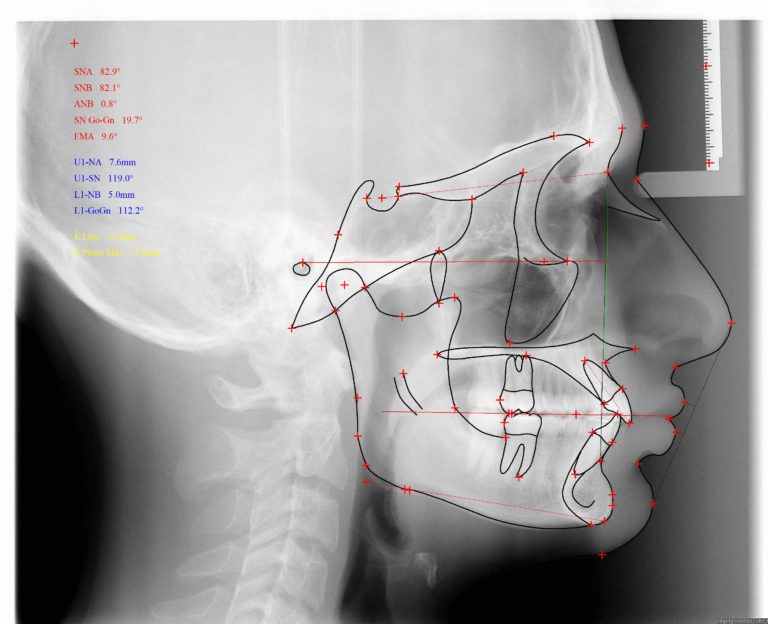

A: We will deliver two .JPG files. An image of your traced ceph X-Ray and an image of your detailed analysis. By default our tracings will be black and we will display ceph points. Below is an example of what you would get from a ABO Analysis in black with all available tracings selected: